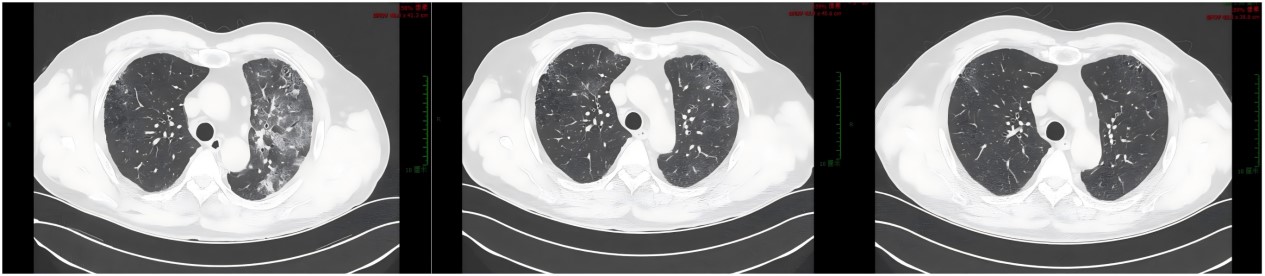

十二通道常规心电图:窦性心律,正常范围心电图。肝胆脾胰超声检查:肝内结石或钙化,胆、脾、胰腺未见明显异常。肾脏超声检查:左、右肾大小分别为:101×51mm、97×51mm,实质回声均匀,皮髓质分界尚清,左右肾皮质厚分别约11mm、9mm,左肾上部见一大小约14×9mm的无回声,边界清,右肾见数个无回声,边界清,其中下部一大小约5×3mm,双肾集合系统五分离,见数个强回声,其中左肾中盏、右肾上盏一长分别约5mm、6mm,提示双肾囊肿、双肾结石。心脏超声检查:升主动脉稍宽,室间隔临界厚。肾动态显像检查结论/诊断:双肾血流灌注明显降低,肾小球滤过功能严重受损,左、右肾GFR分别约11.8ml/min和12.4ml/min。肺部CT提示:双肺所见,多考虑间质性病变,纵隔淋巴结增多;双侧少量胸腔积液,心包积液或心包膜增厚。

鉴于患者存在肺部感染情况,在治疗方面,首先给予丙种球蛋白10g静脉滴注,持续4天,同时开展抗感染及止血治疗。在此前提下,结合患者的经济状况,采用环磷酰胺联合糖皮质激素的诱导缓解方案,并且同步实施降压、生血、降尿酸以及降血脂治疗。在患者第二次入院复查时,其血肌酐水平进一步升高,因此,在原有的环磷酰胺加激素治疗方案基础上,为患者加用了吗替麦考酚酯。此后可见,目前患者经过5次诱导缓解治疗,抗MPO抗体水平明显下降,肺部间质性改变在治疗过程中逐渐减轻直至消失,然而血肌酐及24小时尿蛋白水平虽有所降低,但治疗效果并不显著。